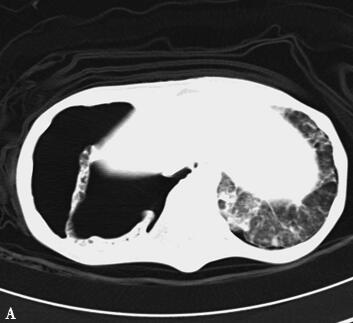

第三阶段(入院后第27~46天):患者病情好转,常规机械通气,SIMV和PS模式:Vt 380ml、PEEP 8cmH2O、PS 15cmH2O、FiO2 50%,监测指脉氧饱和度在93%~97%之间,血压在去甲肾上腺素2μg/min持续静脉泵入可维持在110/60mmHg,但出现并发症:①气胸:反复出现气胸(图5A、B),前后共行胸腔闭式引流术8次,随着肺部感染进一步好转,气胸痊愈(图5C、D);②急性肾衰竭:感染性休克导致肾灌注不足,出现急性肾衰竭,持续无尿状态,床边CRRT治疗;③气道出血:患者出现气道出血,予积极止血、气道管理等处理,病情一度好转,但发病后46天患者再次出现气道出血,氧合难以维持,最终死亡。

图5胸部CT(A、B.气胸C、D.气胸痊愈)